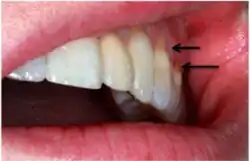

Non-carious cervical lesions on an incisor belonging to Australopithecus africanus. Arrows show the location of the lesions.

Non-carious cervical lesions (NCCLs) are a group of lesions that are characterised by a loss of hard dental tissue at the cementoenamel junction (CEJ) region at the neck of the tooth, without the action of microorganisms or inflammatory processes.[1] These lesions vary in shape from regular depressions that look like a dome or a cup, to deep wedge-shaped defects with the apex pointing inwards.[1] NCCLs can occur either above or below the level of the gum, at any of the surfaces of the teeth.